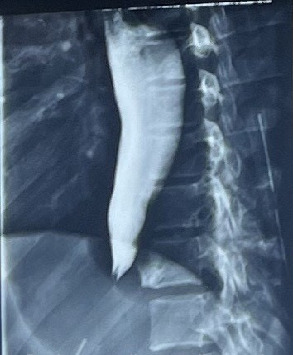

Background: Our case highlights the challenges in diagnosing and managing achalasia cardia, particularly in resource-limited settings and more so in adolescents who fall outside of the typical age range. Case Presentation: We present a case of an 18-year-old female from Uganda who was admitted with a 6-month history of progressive dysphagia, weight loss, and postprandial vomiting. Diagnosis of achalasia cardia was confirmed via endoscopy and barium swallow. Heller cardiomyotomy via open transthoracic approach was performed, but she developed an esophageal perforation, which was successfully managed with repeat thoracotomy and esophageal repair. Complete resolution of achalasia symptoms was achieved at a 5-month follow-up. Conclusion: This case highlights the importance of maintaining a high index of clinical suspicion, especially in young patients, and the significance of informed consent prior to initiating treatment. Additionally, it emphasizes the importance of early recognition of treatment-related complications, such as esophageal perforation, as key to prompt management and improved patient outcomes.